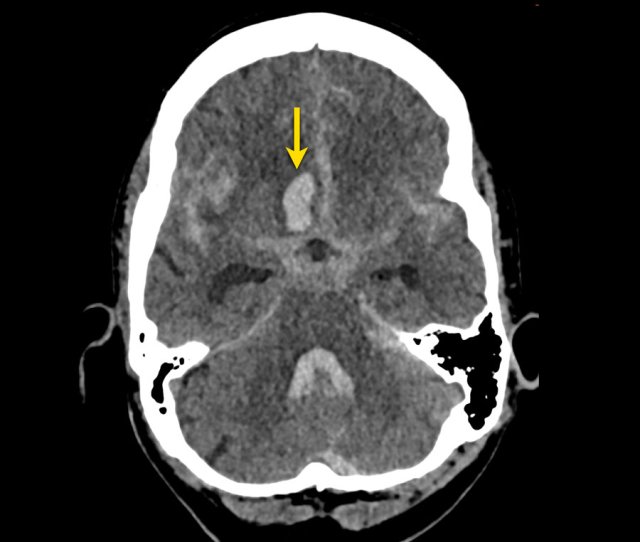

This patient presented with hydrocephalus due to an intraventricular hemorrhage (left image).

Note the very small hyperdensity in the left thalamus, which is the origin of the hemorrhage.

Follow-up one day later (right image).

The patient  underwent surgery with placement of a ventricle drain to treat the hydrocephalus.

Note the hypodense thalamus on the left side with the persistent medially located hyperdense focus.